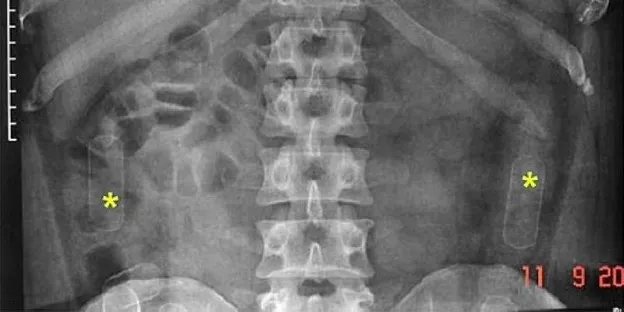

Abdominal Bruising

By: Maha M Farid MBBCh, MSc, PhD, Mohammed Abdelreheim, MSc, FRCPCH, CCT and Marwa Kh. Mohammed, MBBCh, MSc